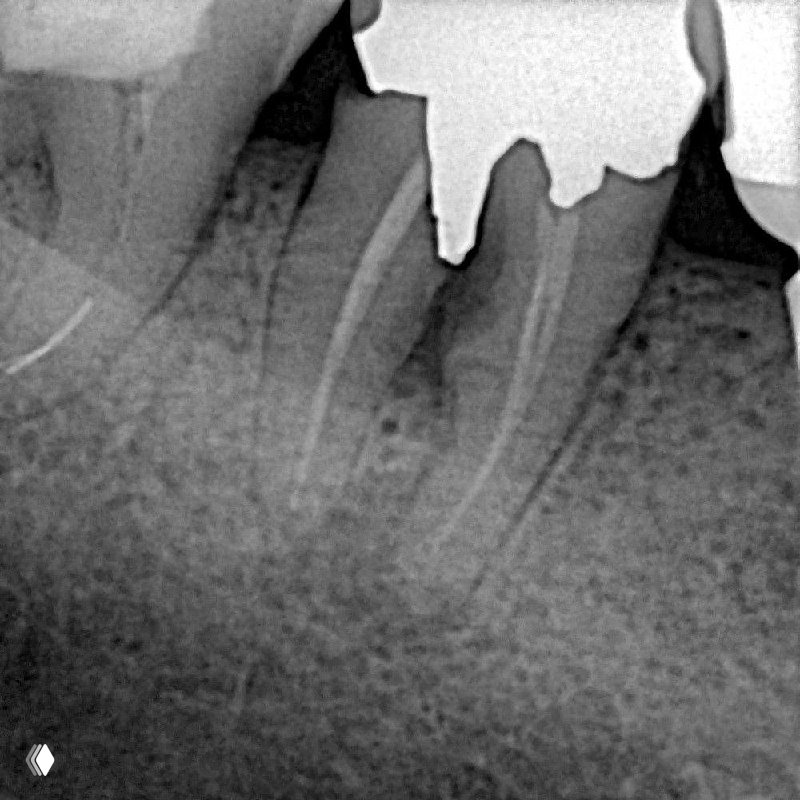

Кейс: крестальная перфорация на 4 мм от альвеолярного гребня с разрежением кости и пародонтальным карманом — в данном случае показано удаление.